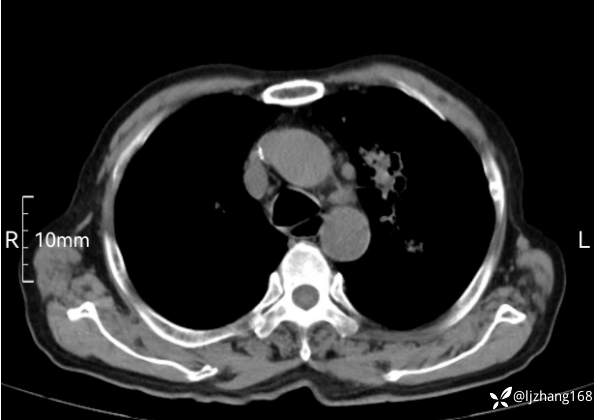

辅助检查:胸部CT:双肺肺气肿,间质性病变,血气分析:PH 7.413, PCO2 29.2mmHg, PO2,81.8mmHg,乳酸 3.3mmol/1,剩余碱-4.0mmol/1,HC03 18.8mmol/1。全血超敏C反应蛋白:超敏C反应蛋白 135.60 mg/L、 白细胞 14x19^9/L,中性粒细胞11.6x10^9/L。